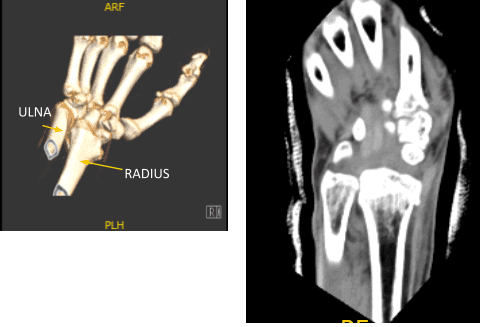

Se presentaron radiografías y se encontraron fracturas intraarticulares del radio distal impactadas, volarmente anguladas y desplazadas volarmente. Sin embargo, no se observa ninguna incongruencia significativa en las articulaciones ni un salto de salida. Hay variación cubital más variación. Fractura mínimamente desplazada en la base del ulna estiloideo. Hay hinchazón de tejidos blandos y derrame articular.

PA y vista lateral del paciente RT 2 semanas después de la operación

Vista AP y lateral de la muñeca RT del paciente 2 semanas postoperatorias